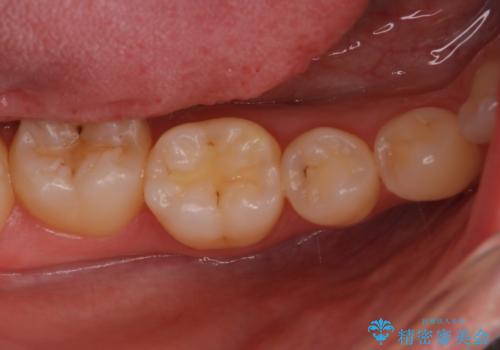

- 検査の結果、虫歯が見つかった患者様です。

白く目立たないものでの治療をご希望されたため、セラミックインレーでの治療となりました。

適合の良いセラミックインレーで修復することで見た目の綺麗さを保ったまま治療することができます。